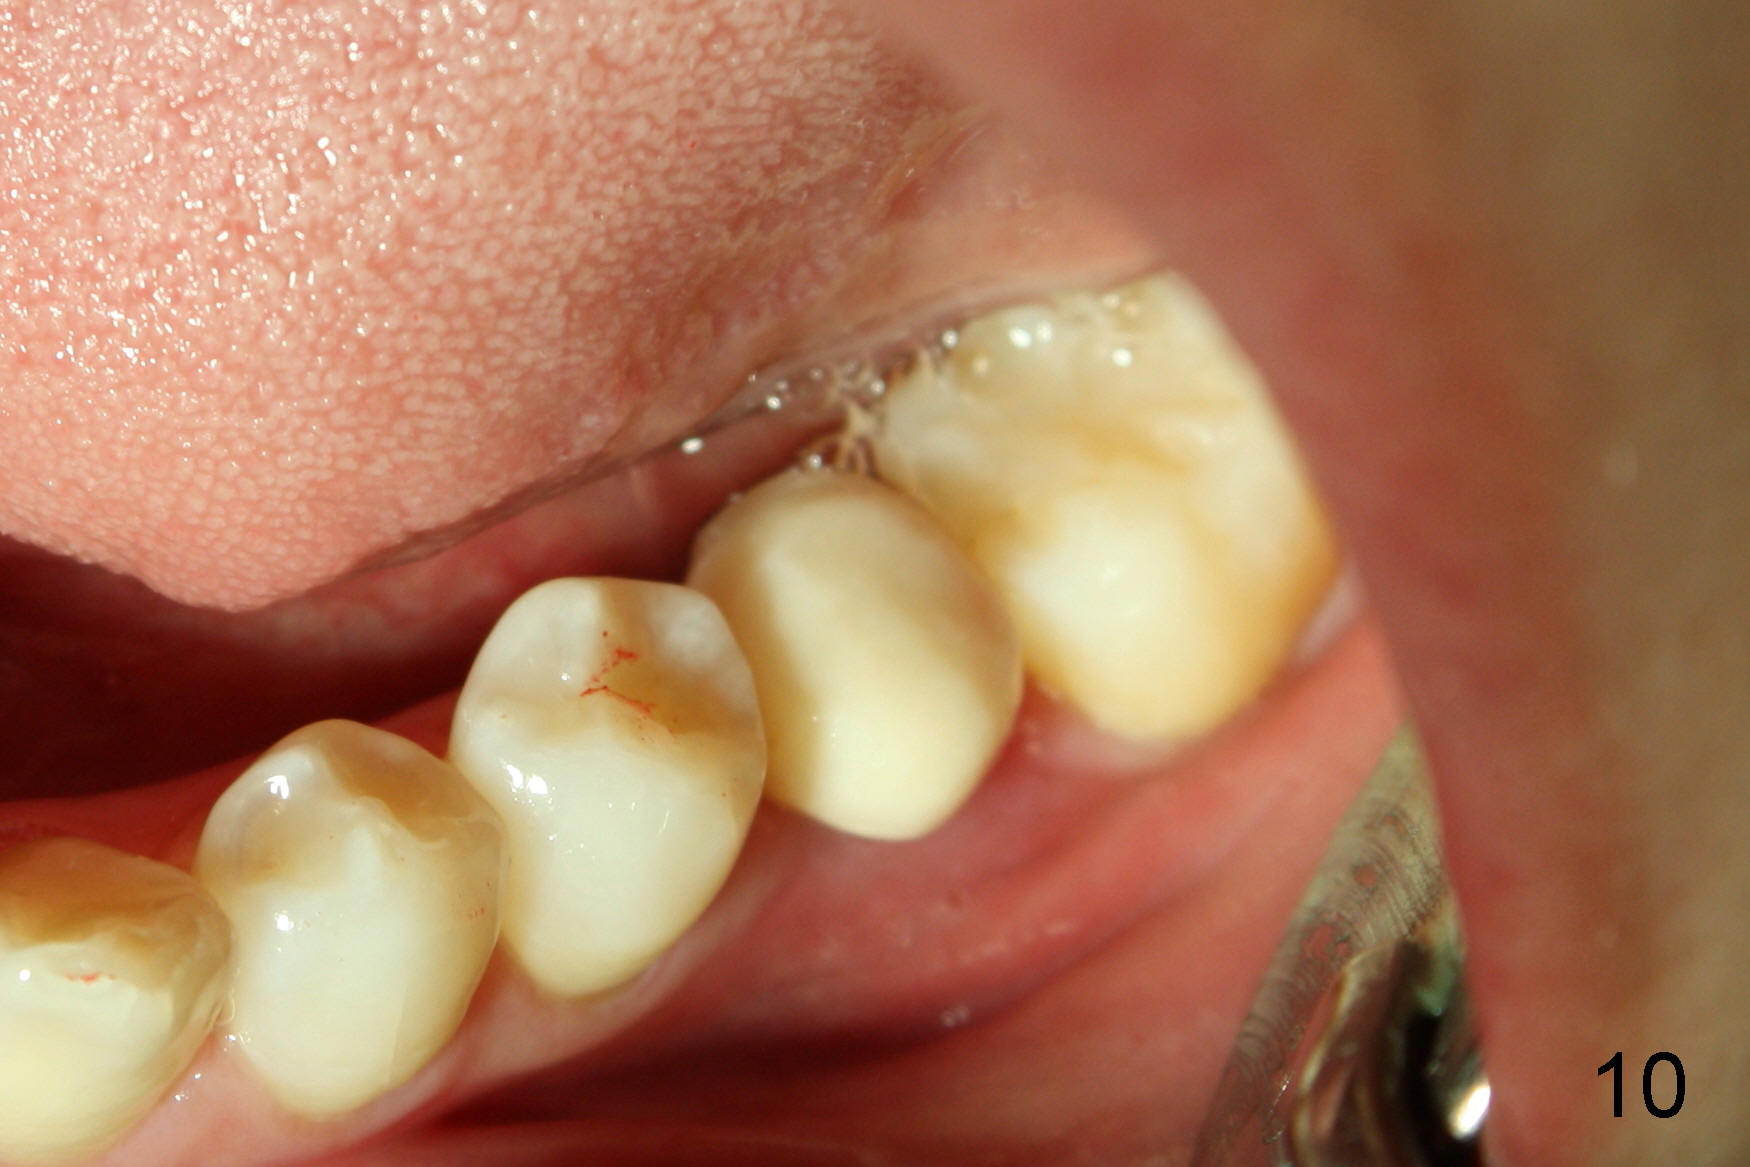

无论如何,只好往前走,下颌临时牙冠加高,之前第二前臼齿远中,第二磨牙近中也要磨去一些,这样第一磨牙也宽些,好看些(图十,与图五对比)。